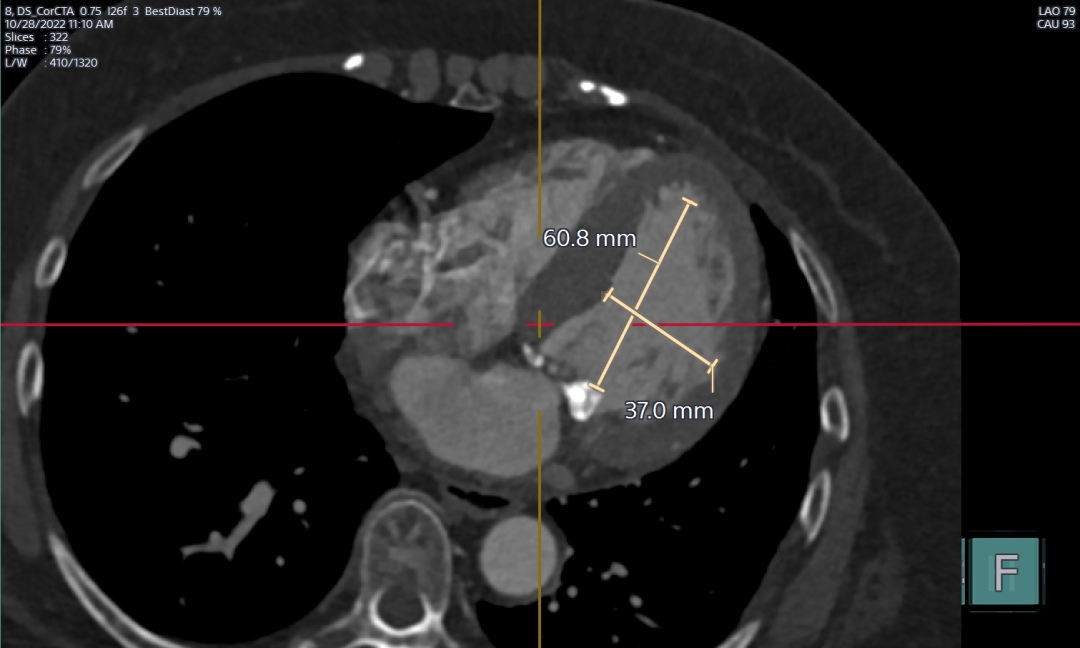

左室前后径

左室上下径、左右径

CT重建分析:

左室前后径:31mm 左室上下径:60.8mm 左室左右径:37mm